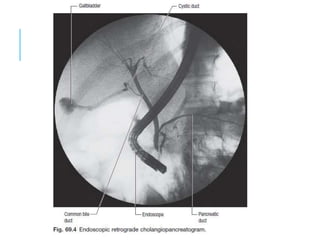

ERCP (ENDOSCOPIC

RETROGRADE CHOLANGIO-

PANCREATOGRAPHY)